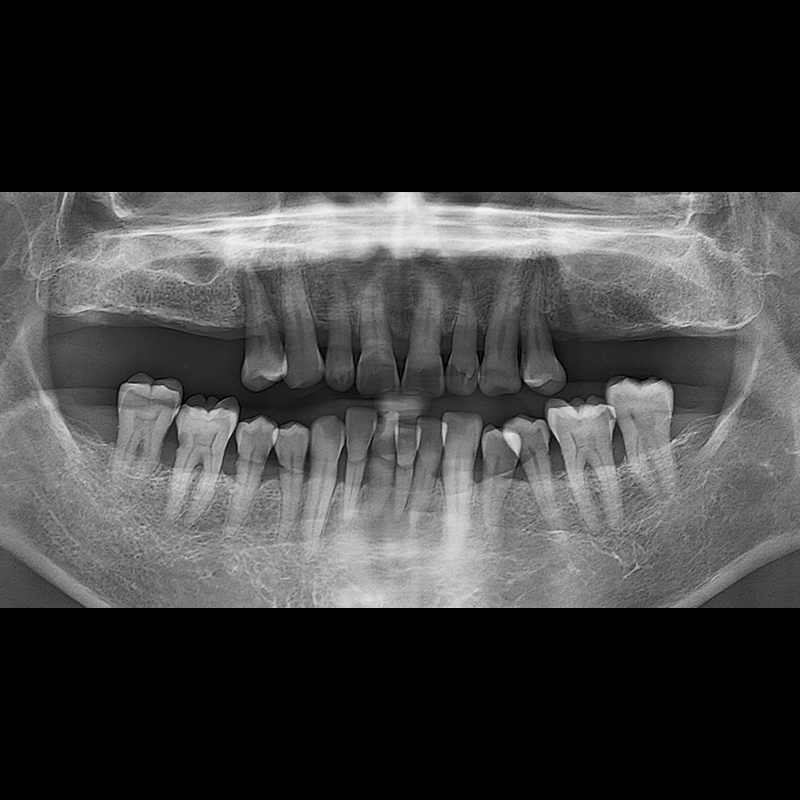

BEFORE AFTER

种植牙前后的照片 2025.05.30

在缺失的牙齿部分和难以挽救的牙齿位置植入了种植牙。